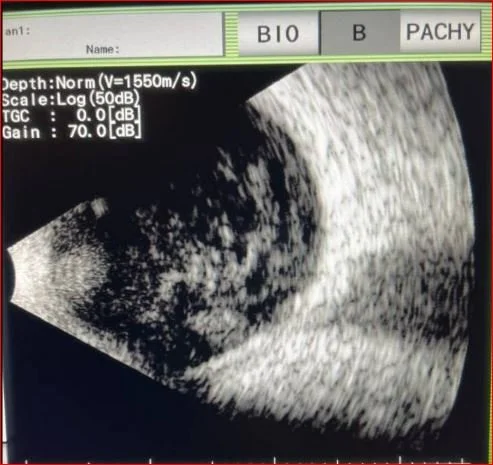

The US of the eye is shown below

What is wrong with his eye?

Our patient had endophthalmitis which is an infection of intraocular fluids.

While not always present, a hypopyon is a clue that endophthalmitis is present. This is a layering of white cells in the anterior chamber of the eye. It is not specific and can be present in eye trauma, uveitis, and autoimmune diseases like Behcet’s.